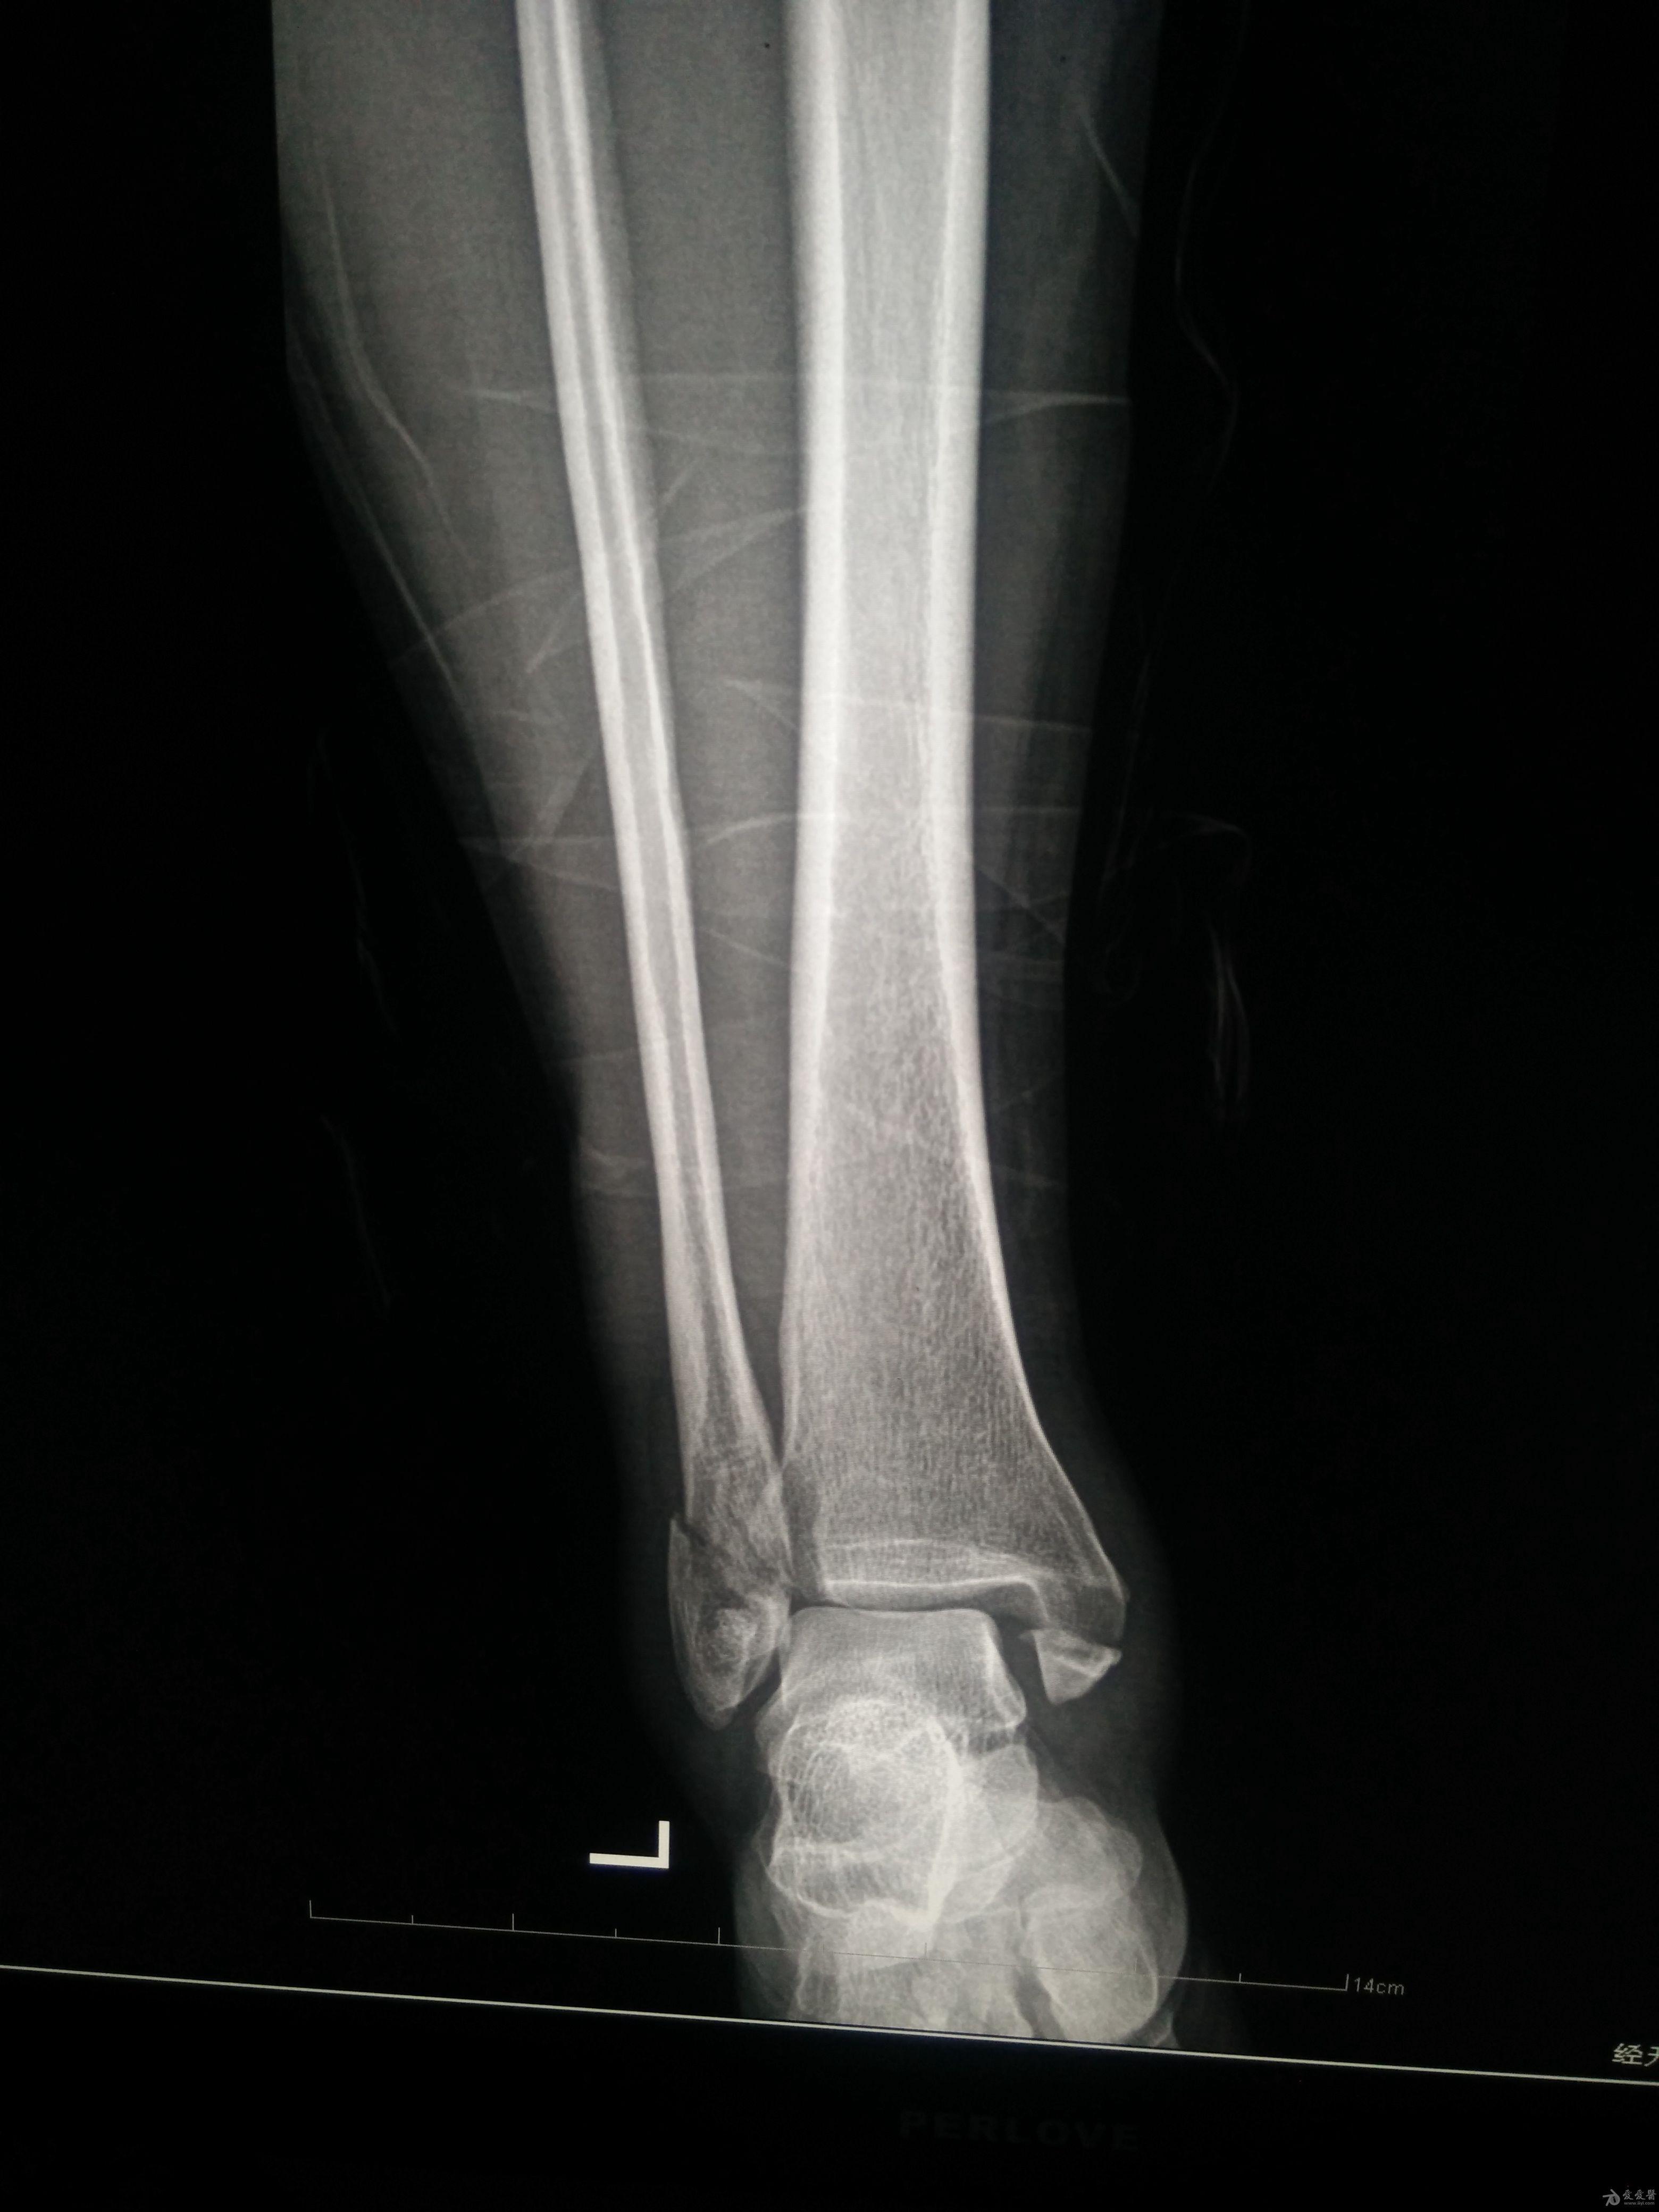

左三踝骨折手术治疗

患者女,外伤后左踝关节活动受限1小时入院,

入院后查体:左踝关节肿胀,活动受限,行DR及左踝关节CT检查,如下图,手术待肿胀消退后行手术治疗,目前愈合良好,请问问各位老师,好久可以下地呀, 下胫腓联合镙钉3个月取呀,

这个下胫腓螺钉真的没有必要打,另外后踝的两枚螺钉怪怪的,从后往前打的,看着钉子帽偏内侧,这个应该在外侧才对,

下胫腓联合单钉固定小心断钉